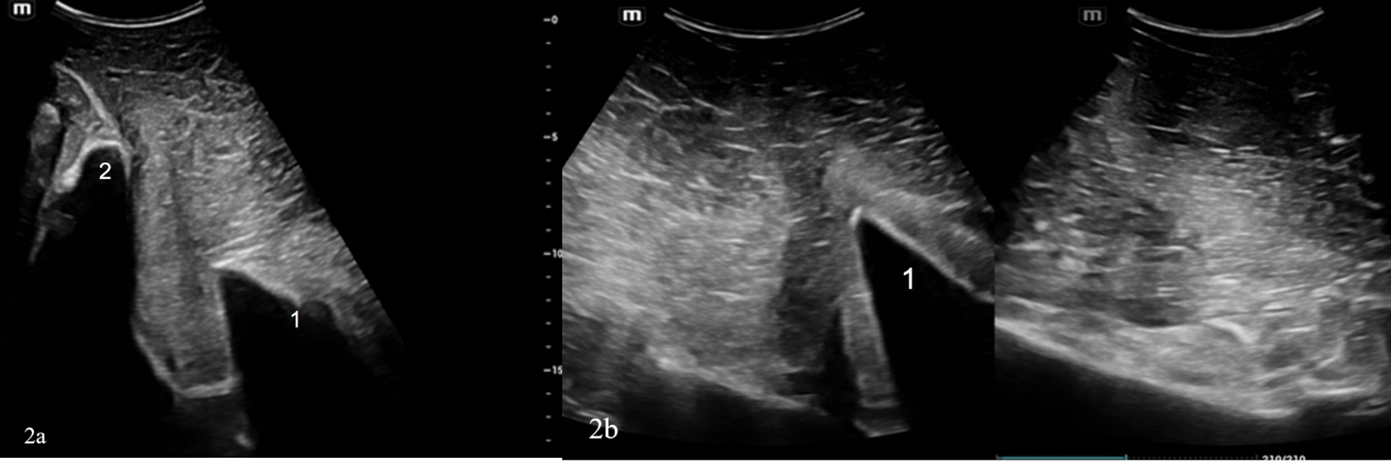

El examen ecográfico externo de la hemipelvis izquierda mostró una fractura aguda, completa y desplazada (aproximadamente 7 cm) en el margen caudal del ala ilíaca izquierda y de la cara craneal del cuerpo ilíaco (figuras 2). El examen de la hemipelvis derecha también evidenció una fractura desplazada del ala ilíaca derecha, ubicada más cerca del plano medio que la izquierda. El contorno del hueso ilíaco derecho se presentó más liso, irregular y grueso; estas características sugerían cambios de remodelación ósea crónica (figuras 3). El abordaje ultrasonográfico transrectal reveló un hematoma ventral y un fragmento óseo a la altura de la articulación sacroilíaca derecha (figuras 4).

Figuras 2: Ecografía hemi-pelvis izquierda. 2a: Corte transversal del ala ilíaca con fractura completa y desplazamiento ventral de la parte lateral (plano medio hacia la izquierda). 2b: Reconstrucción ecográfica longitudinal del ala ilíaca izquierda desplazada (craneal hacia la izquierda). 1: Ala ilíaca lateral. 2: Tubérculo sacro.